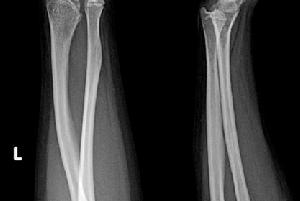

肘外翻肘關節伸直位時肘部外翻角增大,可達30°以上;肘關節活動一般無明顯障礙;晚期肘關節的關節面損傷可引起疼痛。對嚴重外翻病人,由於尺神經處於高張力牽拉狀態,或外傷後因尺神經粘連而經常受到摩擦,可發生遲發性尺神經炎而出現尺神經損傷表現。

肘外翻正常肘關節完全伸直時有一輕度外翻男性約10°,女性約15°,這個外翻角稱為攜帶角。若這個角度增大,即前臂過於外展,稱為肘外翻畸形。肘外翻最常見的原因是未經復位或復位不良的兒童肱骨髁上骨折和肱骨遠端骨折。兒童肱骨內外髁骨折未能及時復位或復位不良、肱骨外髁骨骺早閉或缺血性壞死及未經復位或復位不良的肘關節脫位均可致肘外翻。